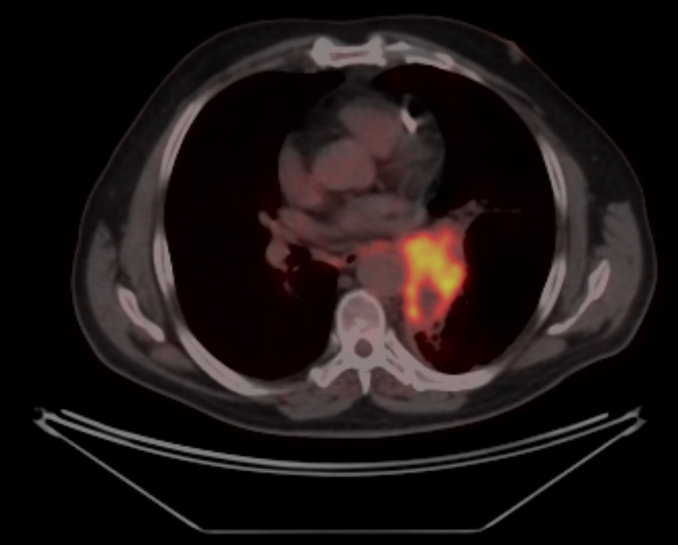

По данным ПЭТ-КТ с 18-ФДГ от 28.06.2022г. по сравнению с исследованием от 29.03.2022г. отмечается:

- уменьшение размеров с некоторым повышением метаболической активности образования в воротах левого легкого;

- уменьшение размеров и снижение метаболической активности медиастинальных лимфоузлов.

В воротах левого легкого сохраняется метаболически активный опухолевый узел с вовлечением главного, нижнедолевого, частично верхнедолевого бронхов, с некоторым уменьшение размеров и ростом метаболической активности, общими размерами около 60х38 мм SUVmax=24,72 (ранее до 83 мм в аксиальной проекции и до 81 мм в краниокаудальной проекции, SUVmax=21.41). Опухоль располагается на расстоянии около 30 мм от киля трахеи с вовлечением левой легочной артерии (обхват около 50%) и тесным прилеганием к нисходящей аорте. В правом легком очаговая и инфильтративная патология легких не определяется.Уменьшение размеров и снижение метаболической активности медиастинальных лимфоузлов, наибольшими размерами/накоплением РФП: подкаринальной группы (7) до 7 мм SUVmax=3,32 (ранее 10 мм, SUVmax=7.49); субаортальной группы (5) до 4 мм SUVmax=2,64 (ранее 8 мм, SUVmax=4.70). Лимфоузлы ворот левого легкого до 7 мм SUVmax=4,36 (ранее сливались с образованием).

В воротах левого легкого сохраняется метаболически активный опухолевый узел с вовлечением главного, нижнедолевого, частично верхнедолевого бронхов, с некоторым уменьшение размеров и ростом метаболической активности, общими размерами около 60х38 мм SUVmax=24,72 (ранее до 83 мм в аксиальной проекции и до 81 мм в краниокаудальной проекции, SUVmax=21.41). Опухоль располагается на расстоянии около 30 мм от киля трахеи с вовлечением левой легочной артерии (обхват около 50%) и тесным прилеганием к нисходящей аорте. В правом легком очаговая и инфильтративная патология легких не определяется.Уменьшение размеров и снижение метаболической активности медиастинальных лимфоузлов, наибольшими размерами/накоплением РФП: подкаринальной группы (7) до 7 мм SUVmax=3,32 (ранее 10 мм, SUVmax=7.49); субаортальной группы (5) до 4 мм SUVmax=2,64 (ранее 8 мм, SUVmax=4.70). Лимфоузлы ворот левого легкого до 7 мм SUVmax=4,36 (ранее сливались с образованием).